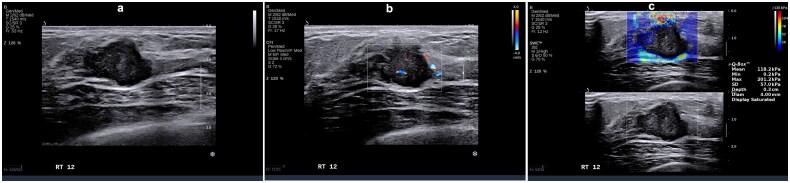

We performed a retrospective analysis encompassing 310 young women with breast cancer. Observations were made regarding the ultrasonography and elastography characteristics of the identified breast lesions. Subsequently, based on immunohistochemistry results patients were classified into five distinct molecular subtypes: luminal A, luminal B (HER2-), luminal B (HER2+), HER2+, and triple-negative breast cancer (TNBC). Clinical, pathological, and ultrasound imaging features were compared among these subtypes using binary logistic regression analysis.

Statistically significant differences were observed in various parameters across the five molecular subtypes ( < 0.05), including tumor size, morphology, margins, calcification, posterior echo features, blood flow (Adler grading), and tumor hardness. Specifically, luminal A subtype exhibited propensity for spiculated margins, lower blood flow grading, and decreased hardness; luminal B subtype was characterized by angular margins; HER2+ subtype manifested higher blood flow grading, calcification, and elevated hardness. Conversely, TNBC subtype displayed smooth margins, absence of calcification, and heightened hardness.

Specific molecular subtypes of breast cancer have unique ultrasonic and elastic imaging characteristics.